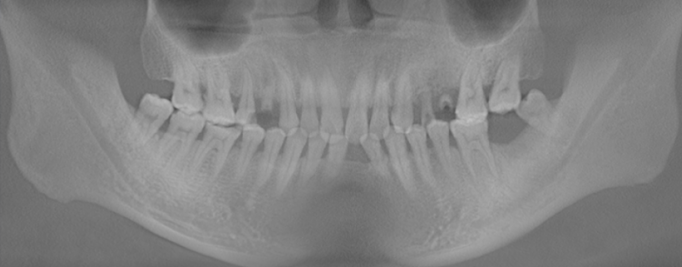

种植前CT

种植前,通过CT可以清晰看到,沈先生的口腔健康状况并不好,多颗蛀牙,左下7号牙缺失,缺牙处牙槽骨已经开始吸收。